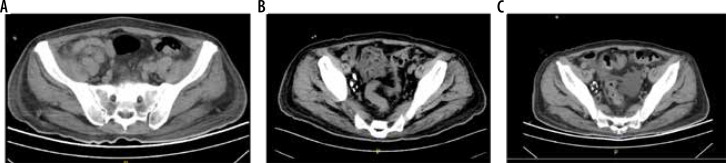

Results: Lymphangiography was successfully performed in all 10 patients. The average dosage of lipiodol used was 4.5 ml (range 3.5-7.0 ml). No procedure-related complications were observed after excluding unrelated factors. During lymphangiography, lipiodol leakage was directly observed in 3 cases, and in the other 5 cases, it was detected through abdominal computed tomography post-lymphangiography. Chylous ascites resolved solely through lymphangiography in 6 patients without requiring additional surgical intervention.